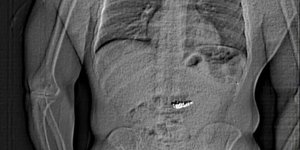

ΚΟΣΜΟΣ 06/03/2025 22:17 Υποπτος για κλοπή κατάπιε διαμαντένια σκουλαρίκια και το έδειξε η ακτινογραφία